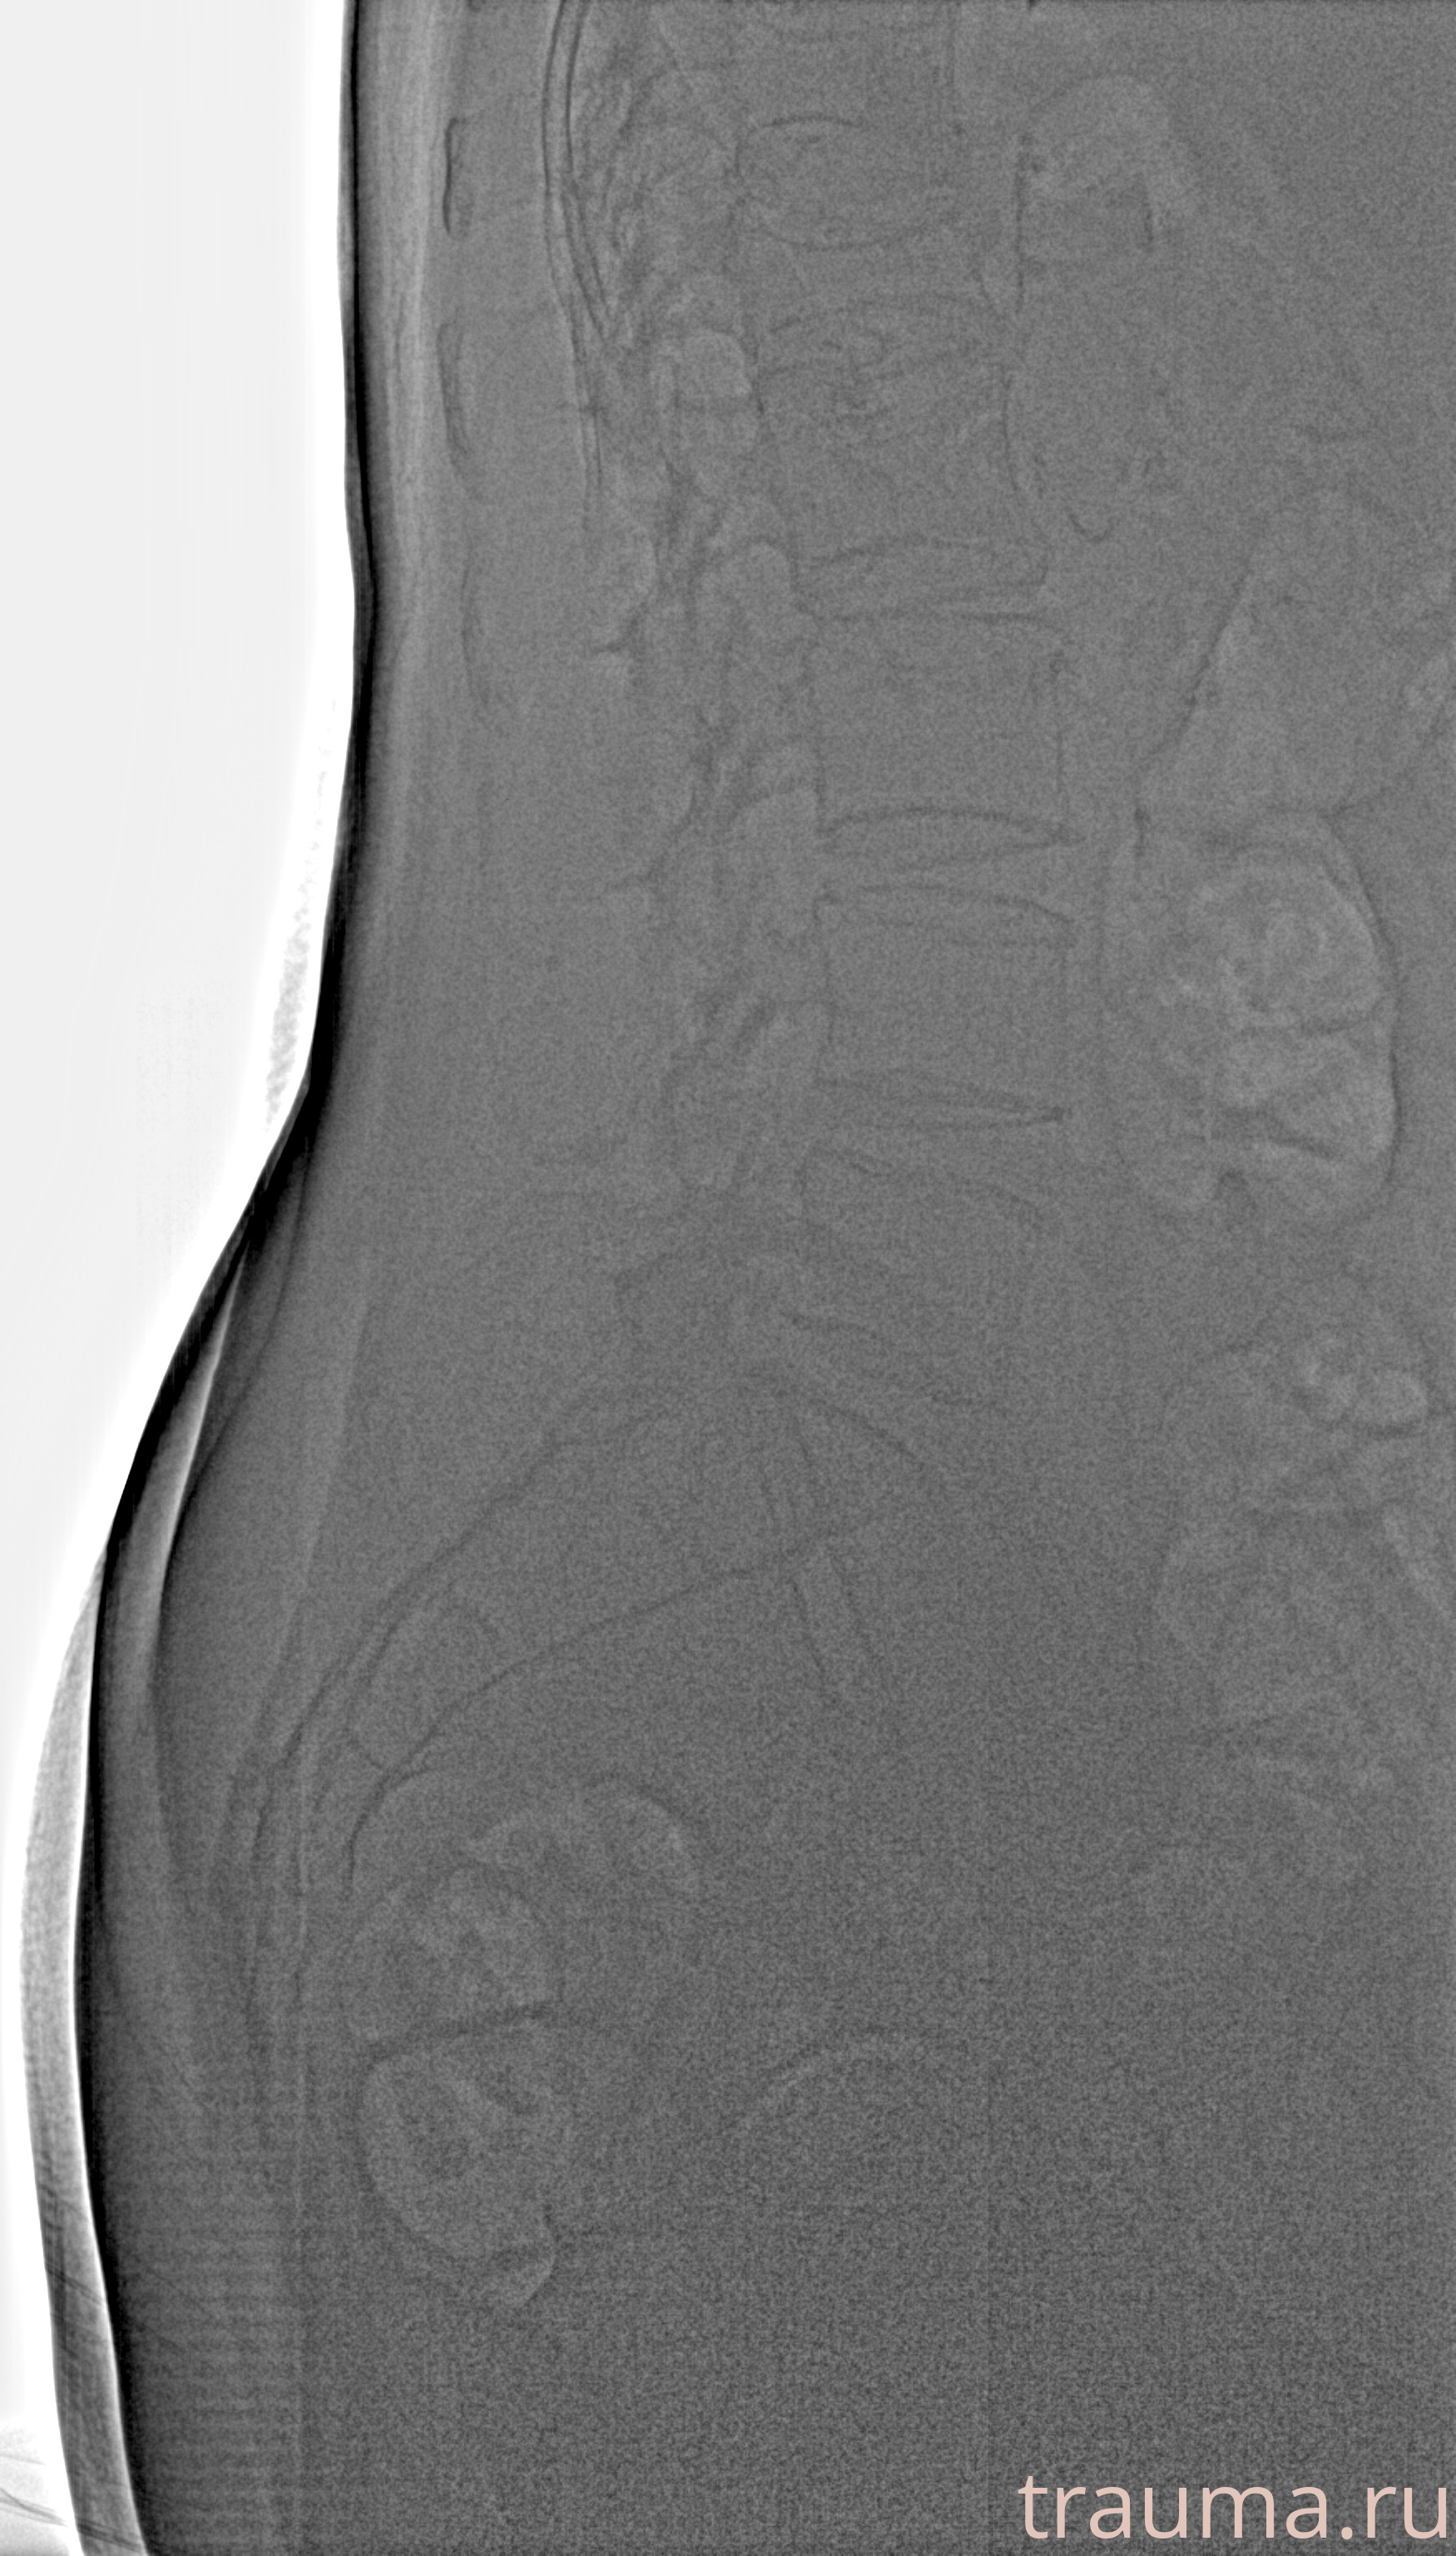

Рентген на дому: по вашему адресу приезжает врач-рентгенолог, травматолог-ортопед с мобильным рентгеновским аппаратом, проводит диагностику травмы или заболевания, делает необходимые рентгенограммы, дает рекомендации по дальнейшему лечению. Получить качественные снимки в домашних условиях возможно благодаря уникальной методике, разработанной МосРентген Центром для института  Склифосовского